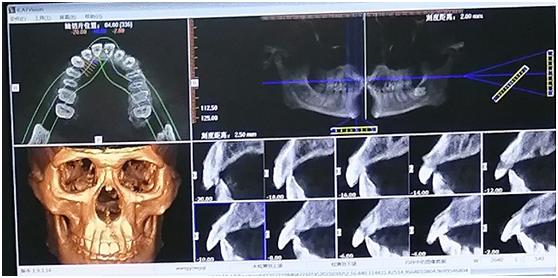

本想着随着时间的延迟,这颗牙会慢慢不疼,逐步转好,可到春节的时候,有几天牙疼似乎严重了,吃饭又受到一些影响,没办法,年后就预约医院的口腔门诊。医生目测一番,又做了牙科的CT:

这还是我第一次知道有牙CT,也是第一次看到自己的骷髅形象,想着百年以后我就变成了这副模样,不禁有点好奇,也有点伤感,虽然这副尊容不惹人待见,但好歹也在这个世界存在过,最后居然成这样了(如果不火化的话)。